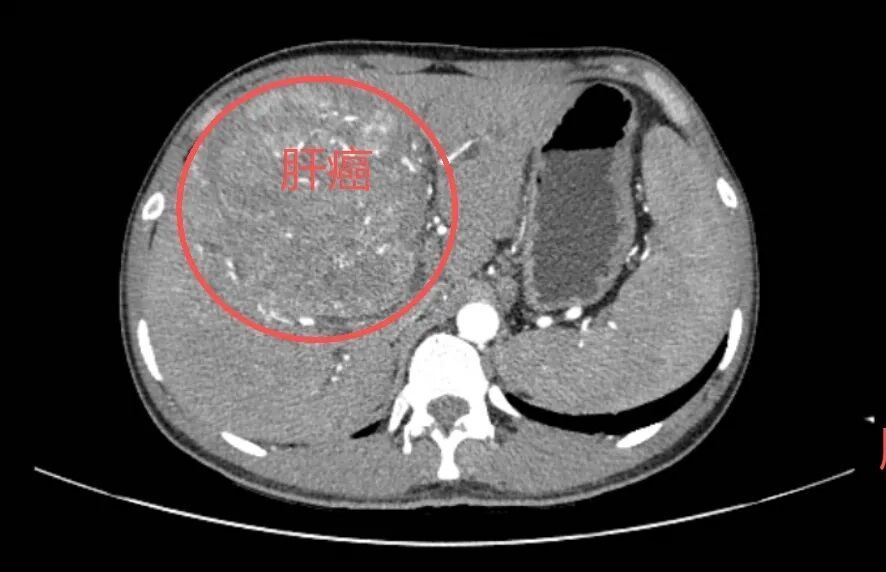

收治了一名年轻的肝癌晚期患者

25岁小王(化名)的CT检查报告上

“肝脏巨大肿瘤”等字样

让人揪心不已